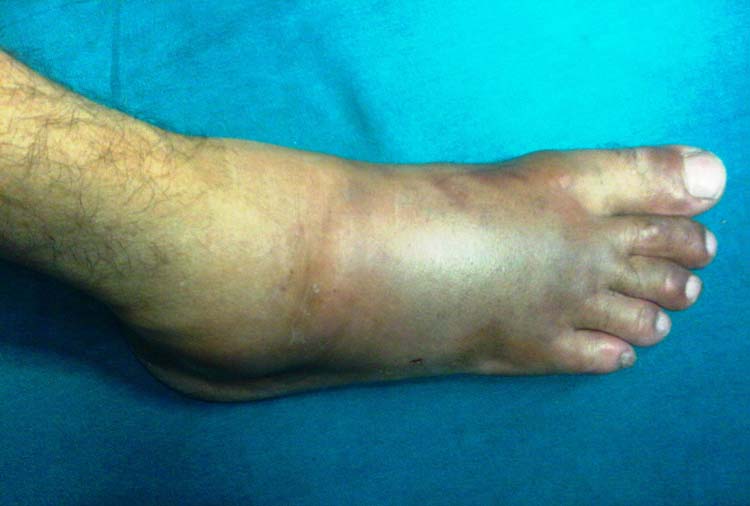

Fasciotomies

Releases fascia to relieve pressure and restore blood flow.